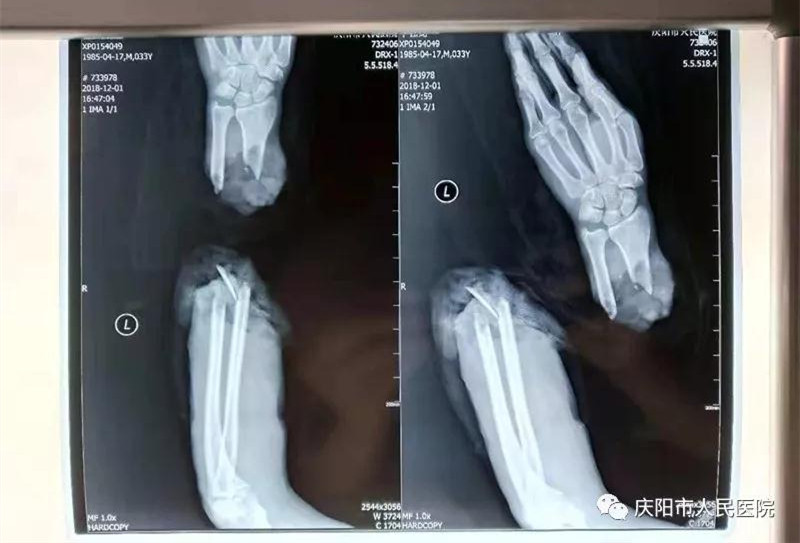

斷肢再植再上新臺階!皯c陽市人民醫(yī)院大夫妙手仁心,又成功完成一例斷肢再植手術(shù)”手足顯微外科團隊在關(guān)鍵時刻,不惜心血和汗水連續(xù)奮戰(zhàn)10多個小時,將完全離斷的患者右前臂再植成功,刷新了斷肢再植的新紀(jì)錄。此病例經(jīng)《隴東報》\掌中慶陽圖文報道,引起社會廣泛關(guān)注和點贊。截止目前,手足顯微外科成功再植成活完全斷離肢體數(shù)10例。